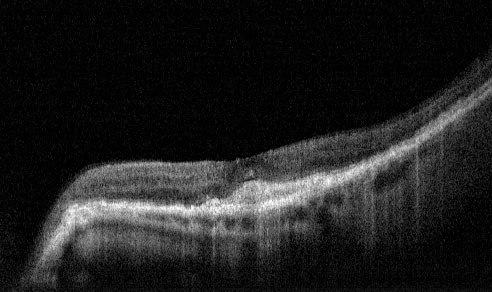

Post Treatment - 1 month following Lucentis Injection